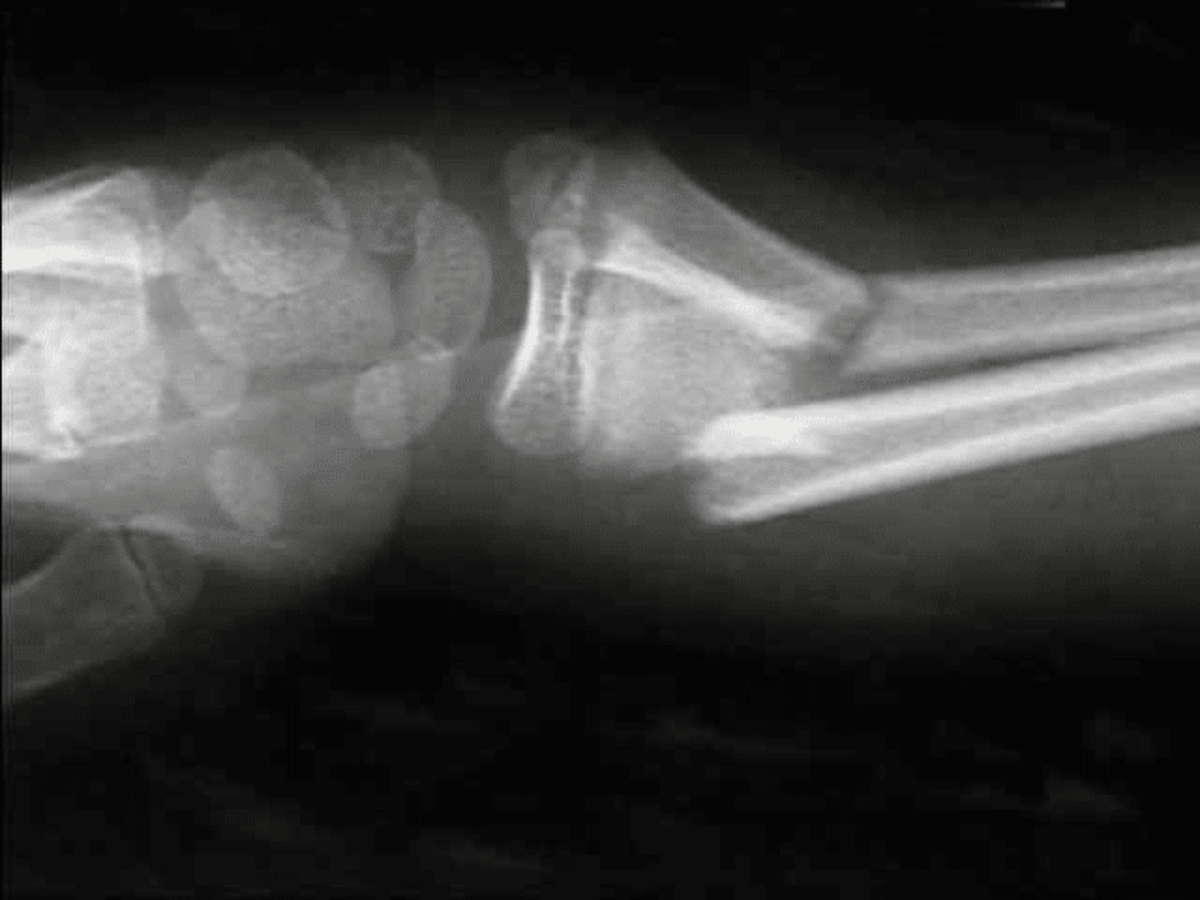

“Maar hij zat echt goed vast!”